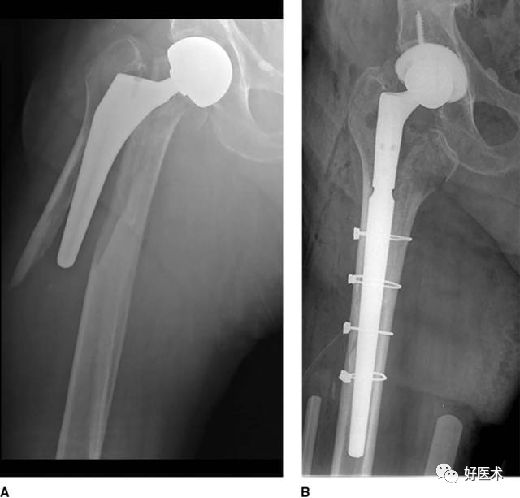

二、假体周围骨折

股骨假体周围骨折:

Vancouver分类系统

否:长柄假体+同种异体骨支撑植骨+钢丝

B2:非移位骨折:假体柄是否稳定?

是:长柄假体+钢丝

-

B3:移位骨折:假体柄是否稳定?

是:同种异体骨支撑植骨钢丝

临床上术式选择看骨折是否影响生物型假体周围起固定作用的部分,若不影响可选择锁定钢板结合钢丝,若影响则需要翻修。